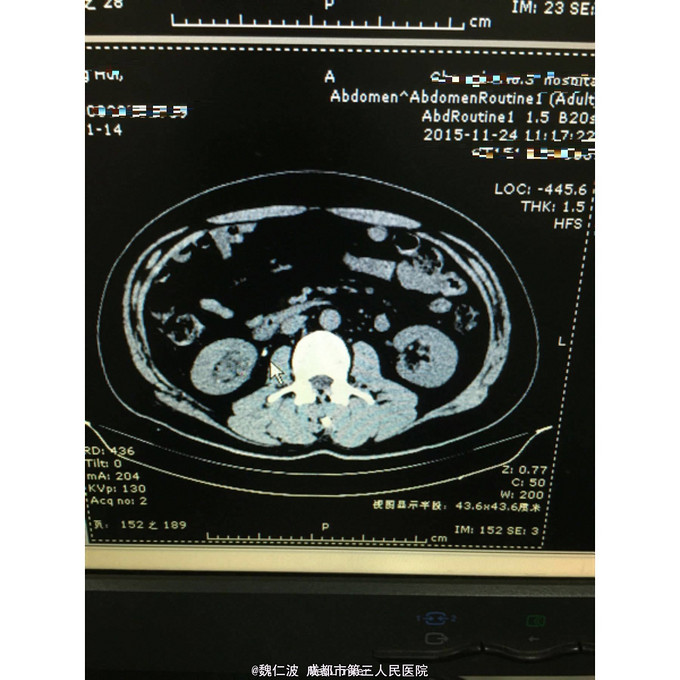

右侧输尿管结石碎石术后3月,发现右侧输尿管上段闭锁4天 3月前因右侧输尿管上端结石行输尿管软镜钬激光碎石,术后恢复可,但拍石稍差,1月后取支架管,术后2月复查右侧肾积水1厘米,3月复查积水5Cm,外院行右肾穿刺造瘘术,发现右侧输尿管上端闭锁,遂来我院。

右侧输尿管上端闭锁,右肾结石,右侧输尿管上端结石 经抗感染治疗后,行开放狭窄段切除,输尿管吻合术,安置F8输尿管支架管。